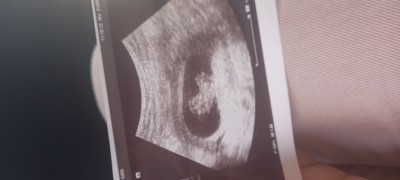

Merhabalar BUGUN DOKTORA GITTIM BEBEGIM 9+4  GUN OLMUS ELLERI OLUSMAMIS DEDI ERKEN MI YOKSA GERIDEN MI GELIYOR

Gebelik haftası 9+2